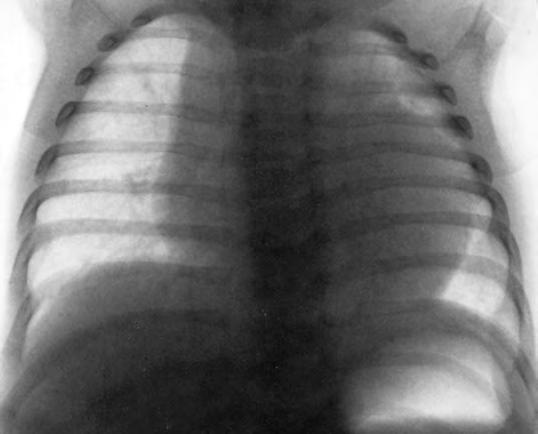

Las extrasístoles son frecuentes, en ocasiones coincidiendo con algún estímulo, como toma de temperatura en el recto, defecación, regurgitación o vómito. Suelen carecer de significación patológica.

El corazón es grande, redondeado, más central y elevado que en otras edades; el latido de la punta se aprecia en el tercer o cuarto espacio intercostal, por fuera de la línea mamilar, debido a la situación más alta del diafragma (Fig. 2.1.4). La presión arterial máxima es de 60 mmHg por término medio, aunque en el control del RN patológico se da mayor importancia a la presión arterial media, que en el niño a término suele ser de 35 a 40 mmHg. El ECG muestra predominio derecho, con una onda S profunda en primera derivación. El aumento de la fragilidad capilar interviene parcialmente en la etiopatogenia de la enfermedad hemorrágica del RN.